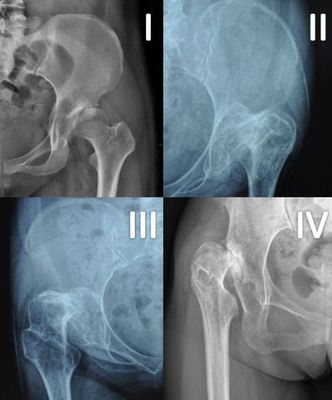

髋关节发育不良图解,髋臼发育不良

髋关节发育不良图片

髋关节发育不良

先天性髋关节发育不良